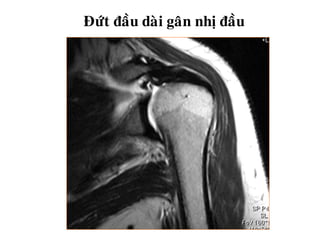

Ñöùt ñaàu daøi gaân nhò ñaàu

Ñöùt ñaàu daøigaân nhò ñaàu